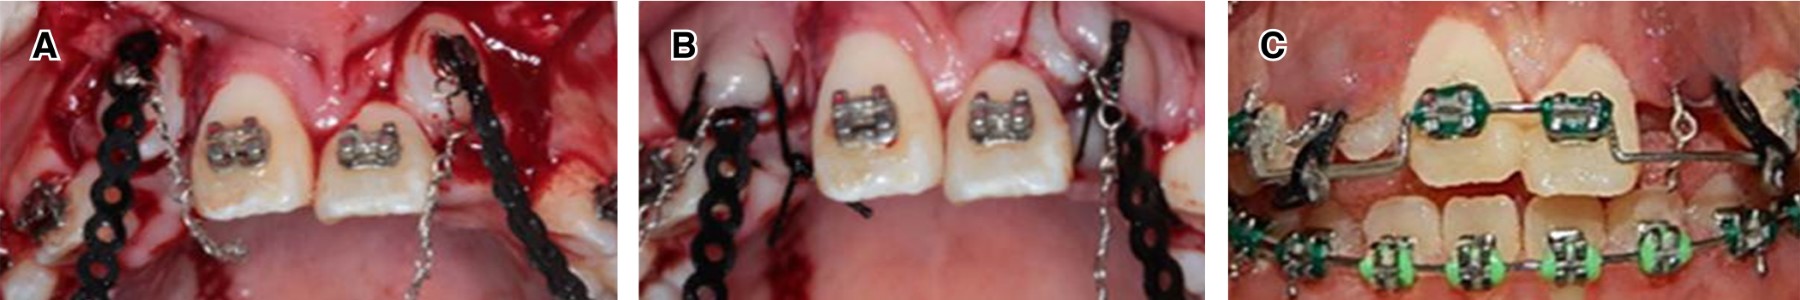

Frontal view of intraoral photographs of treatment in progress. The triple-screw expansion system modified with the traction hooks placed in the vestibular position (Figure 6A). The Hass expander with blue elastomeric chains helped to rotate tooth #11 and to perform traction of tooth #13. Transparent chains were used for traction of tooth #21; green acrylic extensions of the Hass expander were used for the traction arms (Figure 6B). Front view in occlusion and open bite in which the traction of the upper incisors continues (Figure 6C). The bracket was placed and tooth #11 was brought into the arch with a 0.014" NiTi wire.

Space was obtained for the incorporation of these teeth into the dental arch and open surgical windows were performed in two times: in the first intervention for the upper central incisors and upper right lateral incisor (Figure 7).

In the second intervention, bondable buttons with 0. 012" ligature and elastomeric chain for traction into the arch were placed. The images show placement of buttons on canine teeth (Figure 7A), suture (Figure 7B), 0.020 stainless-steel base arch for traction of transposed upper canines (Figure 7C). In the alignment and leveling stage, the correction of maxillary crowding and the handling of jaw spaces was achieved through the sequence of 0.014", 0.016", 0.018", 0.017" × 0.025" upper and lower NiTi archwires, and 0.018" upper and lower stainless-steel wire. To achieve the esthetic objectives, a 5 to 5 upper and lower gingivoplasty was performed, as well as the characterization of the transposed teeth.